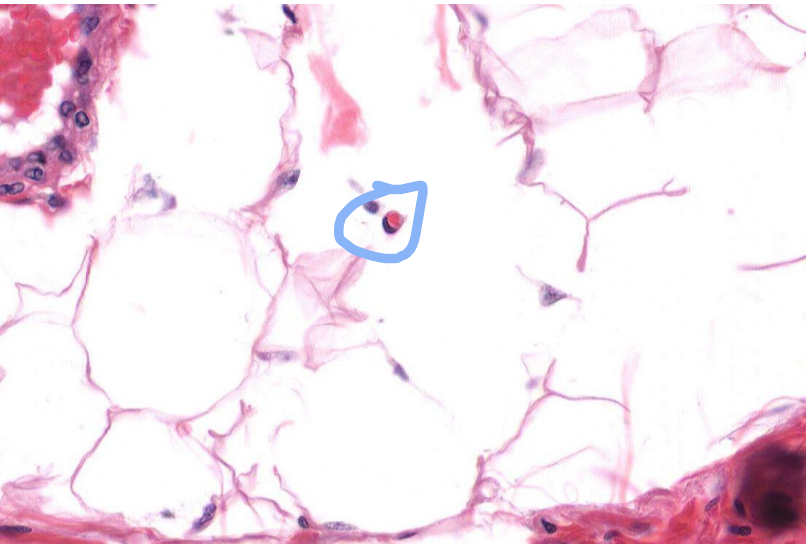

Identify the parts of this structure

A photo of a vein

Green: Valves

Red: RBC

What are valves?

Only seen in veins or lymphatic vessels

Extension of TI.

Identify the structure

Lymphatic vessel